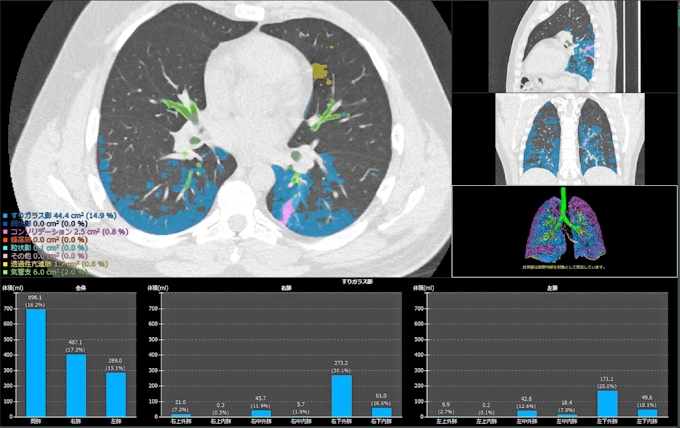

加速するaiによる画像診断支援のいまに迫る Medical Dx

Ai画像診断 Deep Learningによる診断支援 神戸 三宮 公式 北村クリニック

Ai画像診断支援プログラム本格導入へ 集中出版 Shuchu Publishing

Ai画像診断 高質の教師データが強者を決める Beyond Health ビヨンドヘルス

医療業界で期待されるaiによる画像診断の動向 デジタルトランスフォーメーション チャンネル